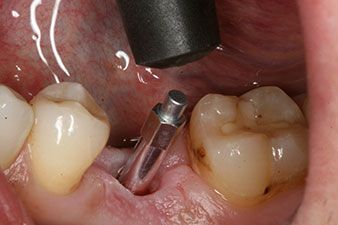

L’implant a été posé comme prévu après élimination complète du tissu de granulation (blueSky, bredent).

Le couple utilisé pour la pose guidée était de 43 Ncm.

En outre, après avoir vissé une tige de mesure (SmartPeg) spécialement conçue pour l'implant, la valeur ISQ a été mesurée à l’aide de la sonde du module W&H Osstell ISQ.

Ce module est fourni en option avec l’Implantmed de W&H et est fixé au moteur d’implantologie (cf. Fig. 11). La valeur ISQ adimensionnelle mesurée immédiatement après l’insertion était de 64 dans l’axe oro-vestibulaire et de 68 dans l’axe mésio-distal (valeur maximale = 100).